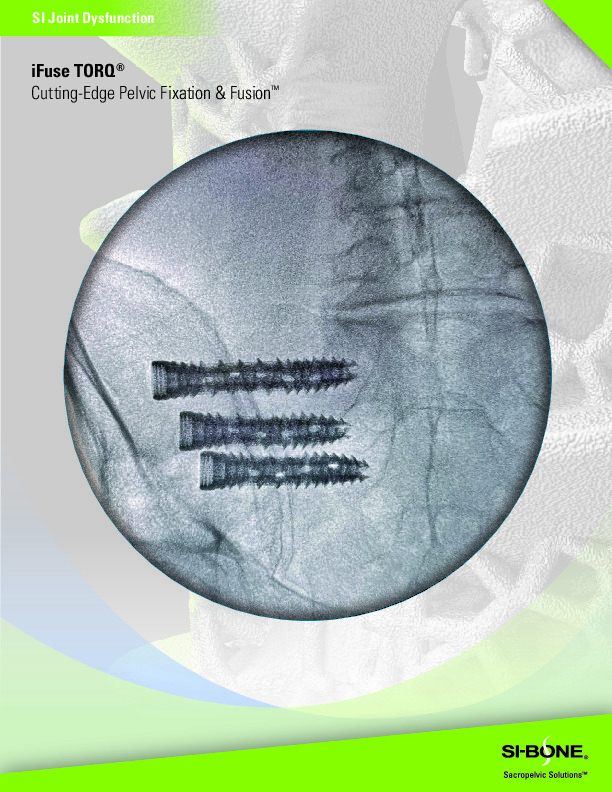

The iFuse TORQ by SI-Bone is a 3D printed titanium screw for use in the fusion and stabilization of the sacroiliac joint. It features a porous open architecture utilizing FuSIon 3D Surface Printed Porous Lattice which allows for osseous integration.

• 3D printed open porous architecture for osseous integration

• Helical Flutes with fenestrations for self-harvesting of autograft

• EZDrive Tip with self drilling and self tapping

• Available diameters:

• 10mm

• 11.5mm

• 13.5mm

• Lengths available

• 35-90mm